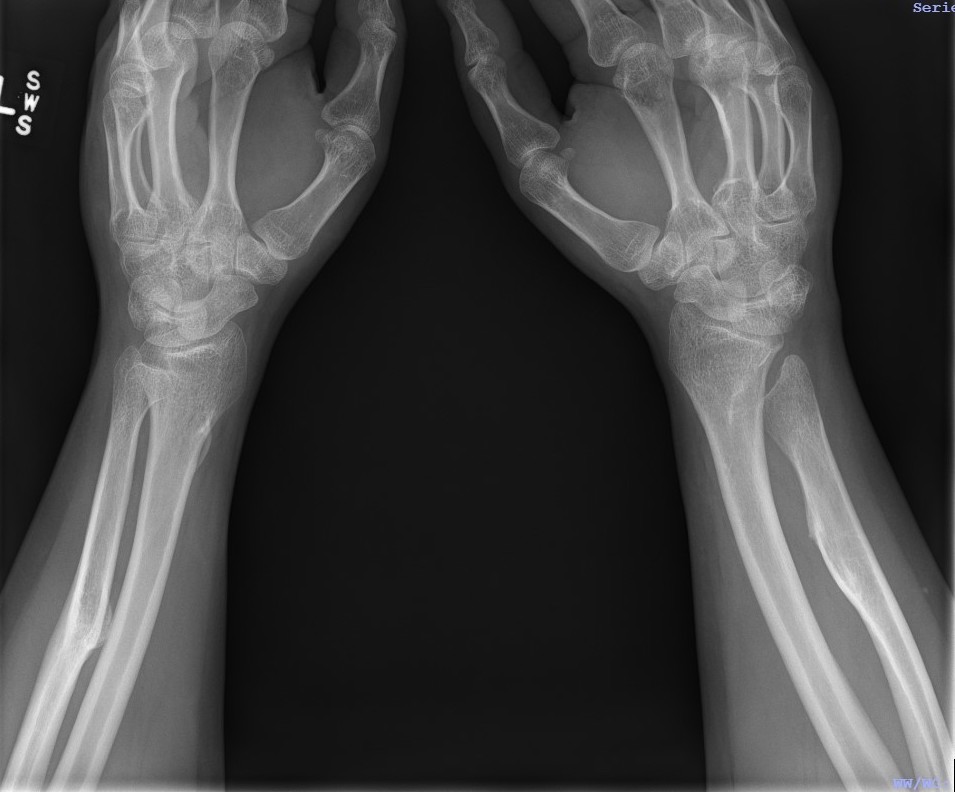

Forearm

- ulnar shortening / radial bowing / ulnar deviation of wrist

- can get radial head dislocation / carpal slip

Osteochondroma ElbowOsteochondromas Forearm 1Osteochondromas Forearm 2

Osteochondromas WristOsteochondromas Wrist LateralMulti OC wrist